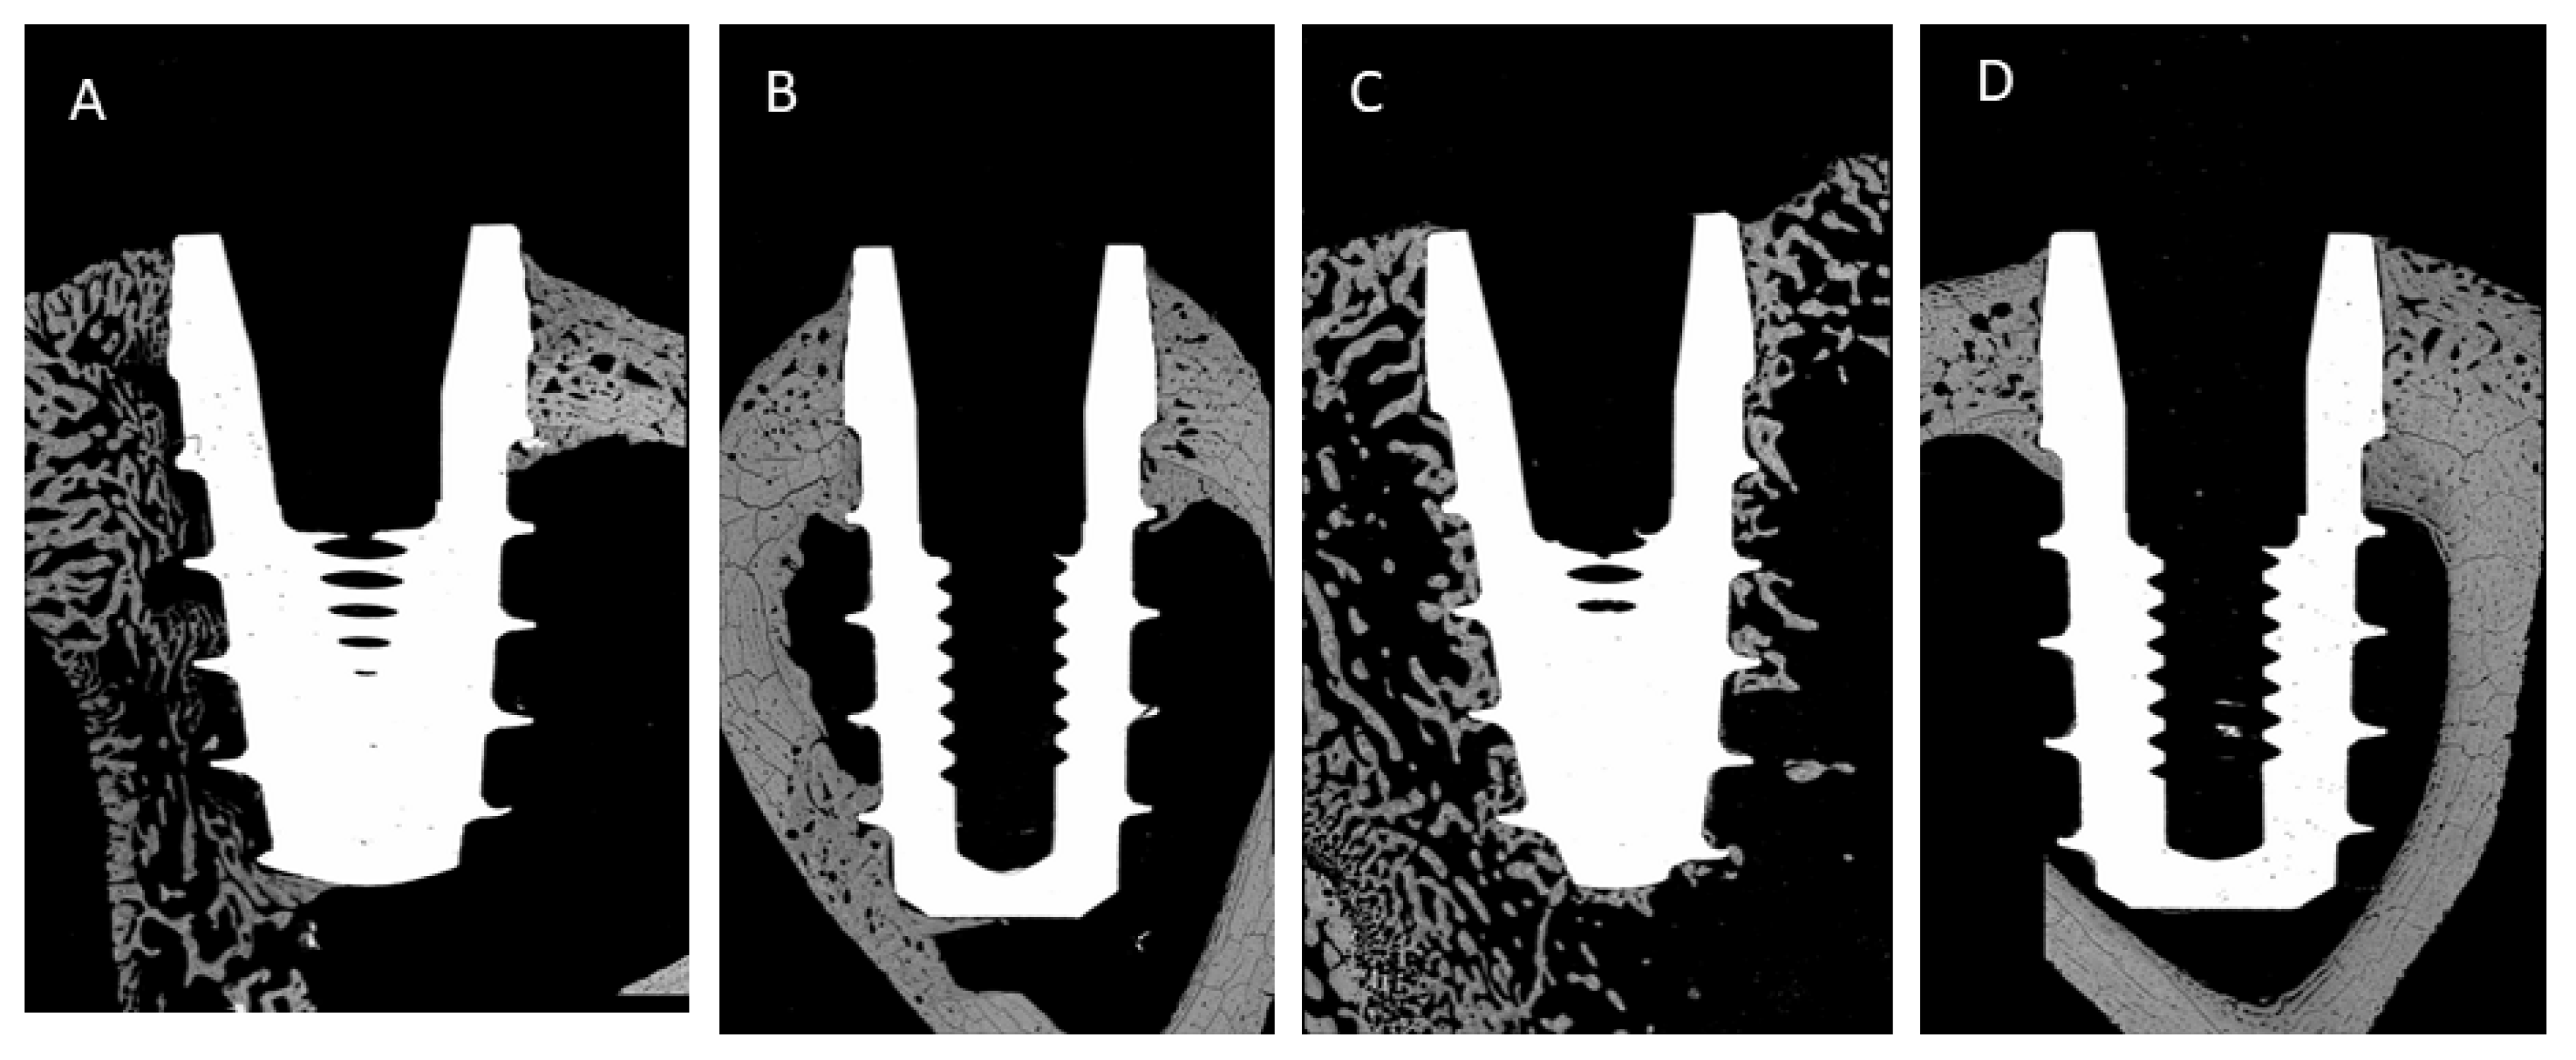

| BIC | 3 Weeks | 6 Weeks |

| Above 0.5 mm | 22% ± 5% | 27% ± 8% |

| Bone level | 29% ± 6% | 33% ± 9% |

| Below 0.5 mm | 35% ± 6% * | 55% ± 8% * |

| BAT | 3 Weeks | 6 Weeks |

| Above 0.5 mm | 26% ± 4% | 32% ± 7% |

| Bone level | 32% ± 9% | 40% ± 8% |

| Below 0.5 mm | 40% ± 6% * | 62% ± 5% * |

| ROI | 3 Weeks | 6 Weeks |

| Above 0.5 mm | 18 ± 7% | 25% ± 6% |

| Bone level | 24% ± 6% | 38% ± 8% |

| Below 0.5 mm | 30% ± 5% * | 55% ± 7% * |